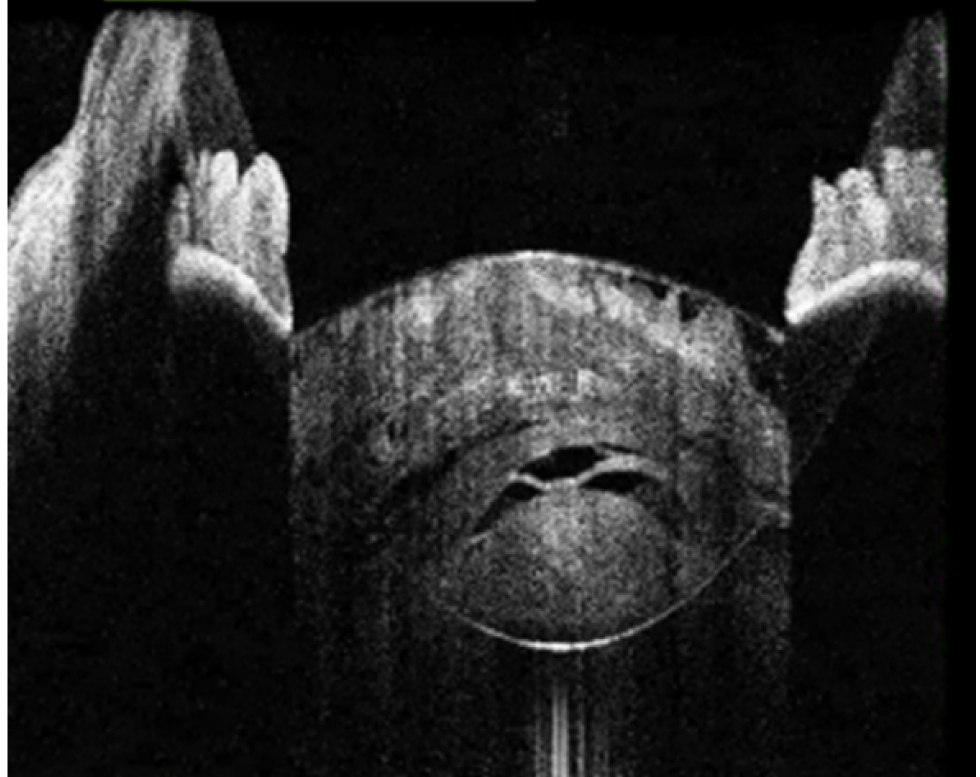

В исследование вошли 196 пациентов (250 глаз) с перезрелой катарактой. Пациенты были разделены на 2 группы (по 125 глаз в каждой группе). Всем пациентам интраоперационно с помощью интегрированной в операционный микроскоп И-ОКТ, Hi-R NEO (HAAG STREIT, Германия), определяли тип перезрелой катаракты (рис. 1–4).

Рис. 3. Тип 3 перезрелой катаракты: выпуклая передняя капсула хрусталика, гиперрефлективные полосы набухших кортикальных волокон, внутрихрусталиковые щели, области однородного вида «матового стекла»